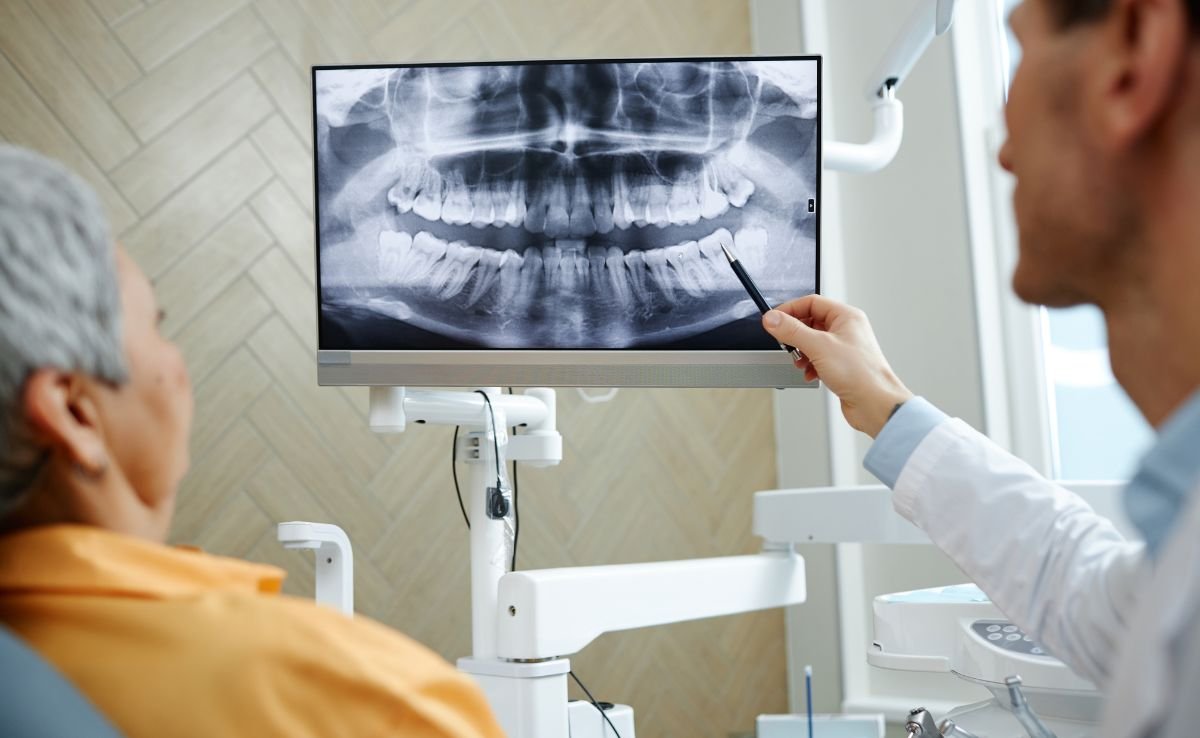

The process starts with undergoing digital imaging such as X-rays or CBCT scans, which help evaluate the condition of your teeth, jawbone, and soft tissues. The surgeon then creates a personalised treatment plan, explains the procedure, and addresses any concerns or risks.